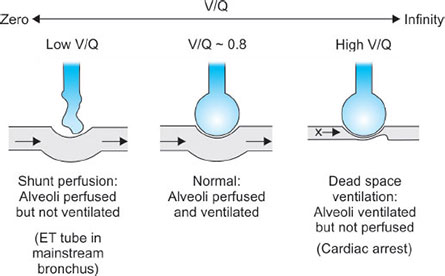

If the lung is being underventilated but perfused as normal then we say that the V/Q ratio is <1 (Fig. 33).

If the lung is under perfused then the V/Q is >1 (Fig. 33).

V/Q = 0 in shunt

V/Q = infinity in dead space.